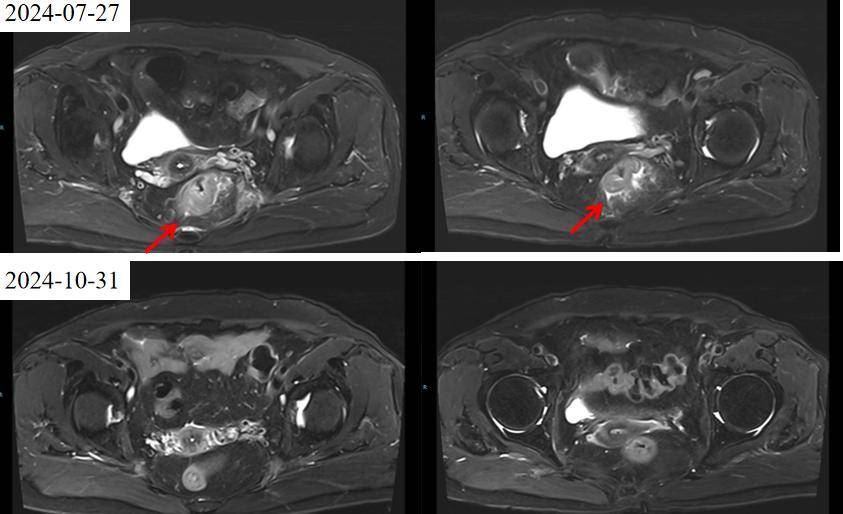

2024年7月27日直肠增强MRI提示:直肠中下段管壁增厚强化(考虑MT)伴周围淋巴结增大,拟T3bN2Mx期,MRF(+)。

疗效评估:2024年10月30日复查CT及MRI,影像评估提示病灶较前明显缩小(肿瘤缩小43%,盆腔淋巴结退缩),疗效评估为部分缓解(PR)。